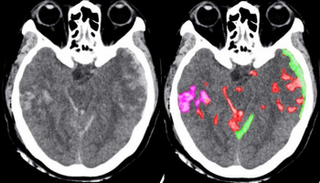

قريبا جدا سوف يصبح الذكاء الاصطناعي مساعدا للأطباء في توقيع الكشف على الحالات المتوقع تعرضها لنزيف المخ